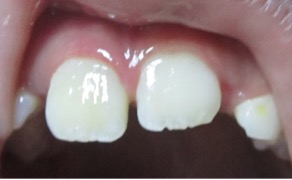

Se presenta el caso de un paciente de sexo femenino, de 8 años de edad. La paciente acudió acompañada con su padre al servicio de endodoncia del Instituto Nacional de Salud del Niño en Lima- Perú, con antecedentes de traumatismo dental, en sector antero superior y con dolor espontáneo. Al examen clínico intraoral, se evaluó que el diente 11 presentaba una ligera movilidad dental y al examen radiográfico se observó diente 11 no vital, ligero ensanchamiento del ligamento periodontal y desarrollo radicular en estadio 8 de Nolla (Figura 1 y 2). Se evaluó el caso y se realizó la explicación de las ventajas y desventajas del tratamiento de revascularización pulpar al padre de familia y se procedió a la firma del consentimiento informado para el tratamiento.

Figura 1: Pza. 11 con antecedentes de traumatismo alveolo dentario.